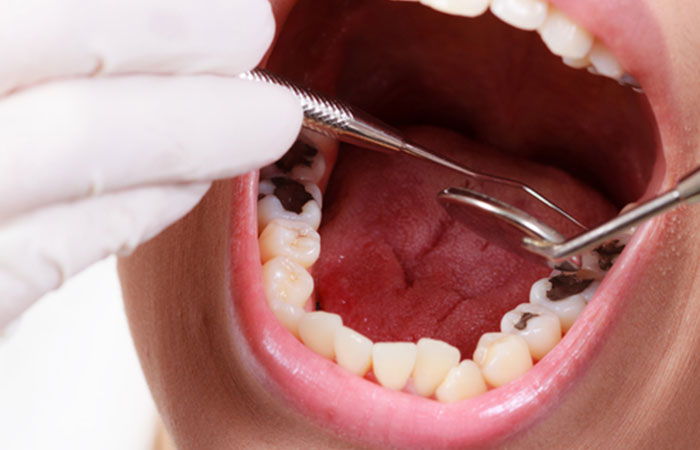

Caries